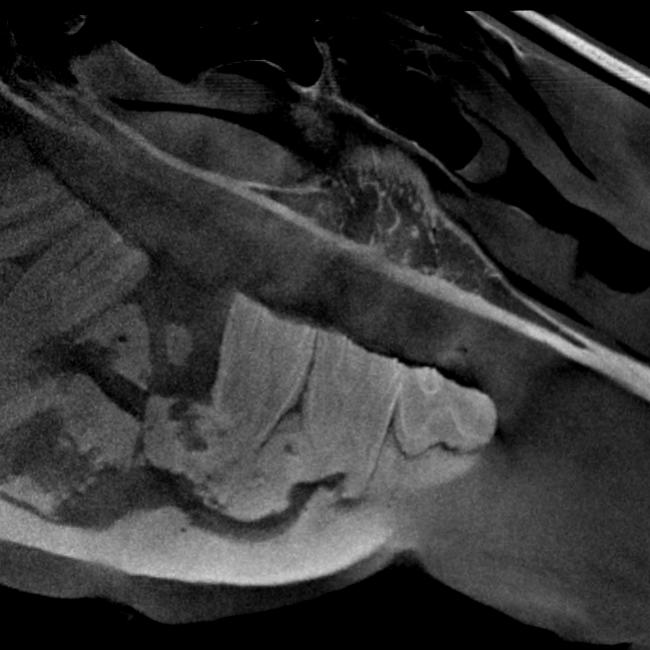

Our High Definition Volumetric Imaging (HDVI) technology represents the most advanced stage of Flat Panel CT technology. It offers exceptional diagnostic imaging for both hard and soft tissues, in diagnostic settings and intraoperative theaters. It is the gold standard for orthopedic applications.

Pegaso enhances safety and usability by enabling the scanning of a standing horse’s head, neck, and limbs.

Pegaso scans head, neck and limbs of the standing horse